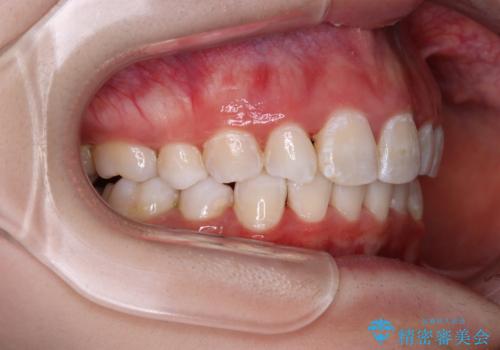

叢生・ディープバイト・突出 ワイヤー装置での抜歯矯正で全てを解決

- 前歯のデコボコと唇の閉じにくさを気にして来院された患者様です。

極端な出っ歯という訳ではありませんでしたが、叢生が強かったため、上下左右の第一小臼歯4本を抜歯し、少しでも口元の突出感を改善できるよう治療計画を立案しました。

下顎前歯が隠れるほどのディープバイトであり、それによる顎の負担も大きかったため、ディープバイトもしっかりと改善できるよう、表側のワイヤー装置にて矯正治療を行うこととしました。

ディープバイトは、治療を行っていた我々も驚くほど、短期間で劇的に改善することができました。

骨格的に下顎骨が左側にシフトしていたため、上下正中の位置や左側臼歯部の咬合を理想的に仕上げることはできませんでしたが、非常に綺麗な口元を達成することができました。